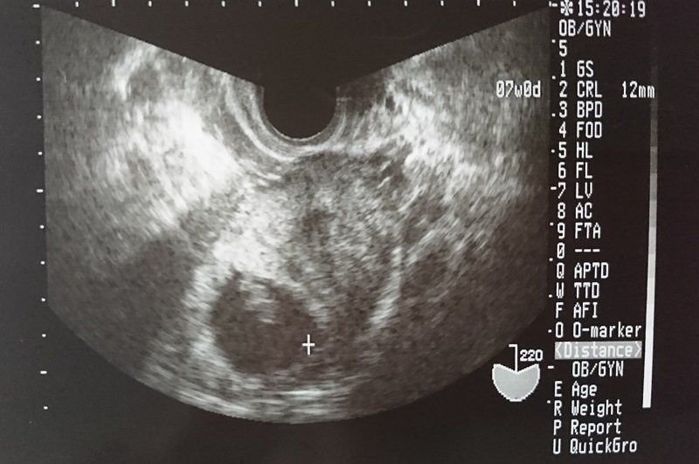

妊娠9週目のエコー写真 予定日が決まりました

赤ちゃんの頭と体が分かれて見える時期だそうです。確かにエコー写真を見ても、頭と体が分かれて人間らしくなってきました。赤ちゃんの体の大きさは丁度“そら豆”くらいになるようです。2週間後の妊婦健診が待ち遠しいです。